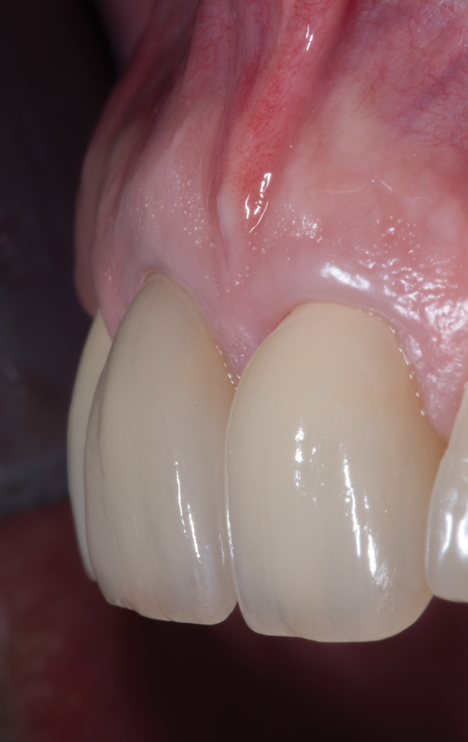

Fig 5. Preoperative clinical image of tooth No. 8 (1:1). A thin scalloped phenotype, prone to collapse upon removal of the tooth, was evident.

Figure 5

Fig 9. Facial view of clinical appearance of facial tissues at 1-year postoperative follow-up.

Figure 9

Fig 10. Oblique view of single-tooth implant No. 8 (1:1) treated with PET. Note the excellent retention of soft-tissue form around the restoration reflecting maintenance of the supporting buccal plate of bone.

Figure 10